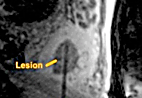

sharpened_Untitled3-1

Results are confirmed with MR images. The laser applicator is removed. The entire procedure, including preparation time, lasts approximately 1.5 to 2 hours.